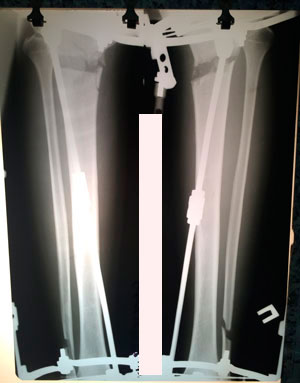

Исходник - 25 лет.

Диагноз: варусная деформация голеней. Удлинение голеней на 2 см (с целью увеличения роста)

Дата операции - 10.07.2019г.